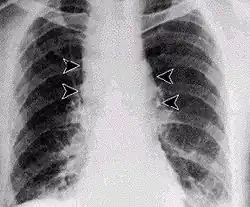

- Bij mensen die met vee of huiden omgaan treedt soms een zwarte pijnloze steenpuist-achtige ontsteking van de huid op (zie foto), de pustula maligna. Deze geneest in de regel zonder ernstige gevolgen; als zij niet wordt behandeld kan de kans op overlijden echter oplopen tot 20%.

Huidvorm

De huidvorm is de vorm van miltvuur die in 95% van de gevallen voorkomt en het is de minst ernstige vorm. Het ontstaat na besmetting via de huid. Er vormt zich een pijnloos maar jeukend bultje op de handen, in de nek of het gezicht. Na 2-3 dagen gaat dit over in een blaartje en daarna in een zweer die bedekt wordt met een zwarte korst. Daaromheen ontstaat vaak een flinke zwelling en een krans van blaasjes. Nadat de korst weg is, blijft een litteken altijd zichtbaar. Soms gaat de huidzweer gepaard met hoofdpijn en koorts. Behandeling met antibiotica zorgt er niet voor dat de zweren sneller genezen, maar voorkomt wel sterfte doordat de bacterie geremd wordt. Als er niet behandeld wordt, kan de ziekte in 10 tot 20 % van de gevallen de dood betekenen.